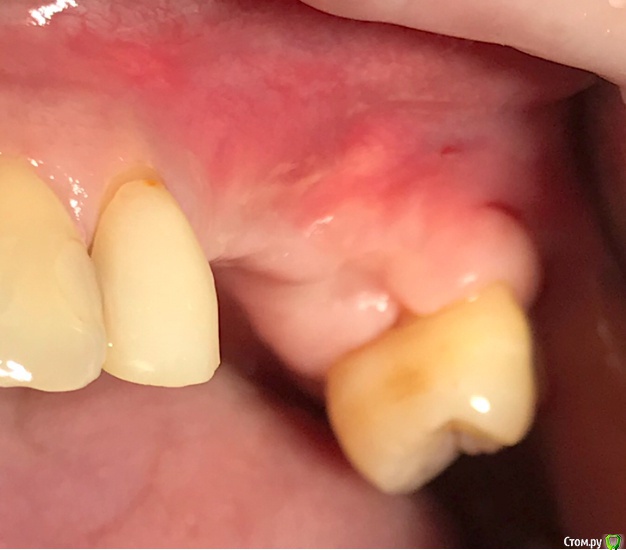

колесников Опубликовано 27 сентября, 2019 Автор Поделиться Опубликовано 27 сентября, 2019 Улучшение объема и качества мягких тканей в пришеечной области у ранее поставленных имплантов ,посредством тоннельной костной пластики. Объём 0,5г. Вид через 6 мес. 3 Ссылка на комментарий